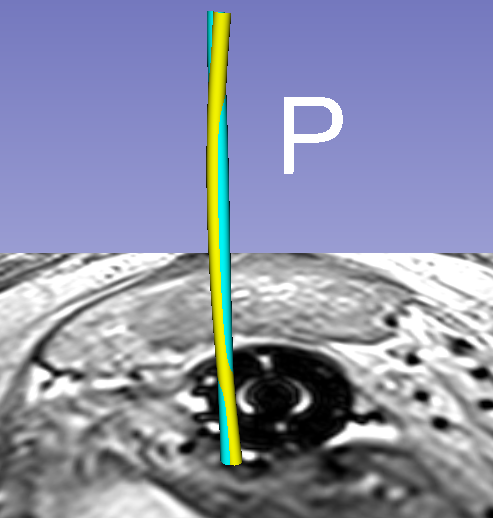

Qualitative results for two different examples can be seen in Fig. 3 and demo movies444https://goo.gl/fLsa2R. The top rows illustrates cross-sectional and 3D rendered views of automated segmentations of a catheter array. The overlap of the colored catheters shows how well they agree. The bottom row of this figure illustrates the case of one particular catheter from the experiments, and specifically how both the model and image guidance are necessary to achieve correct segmentation.